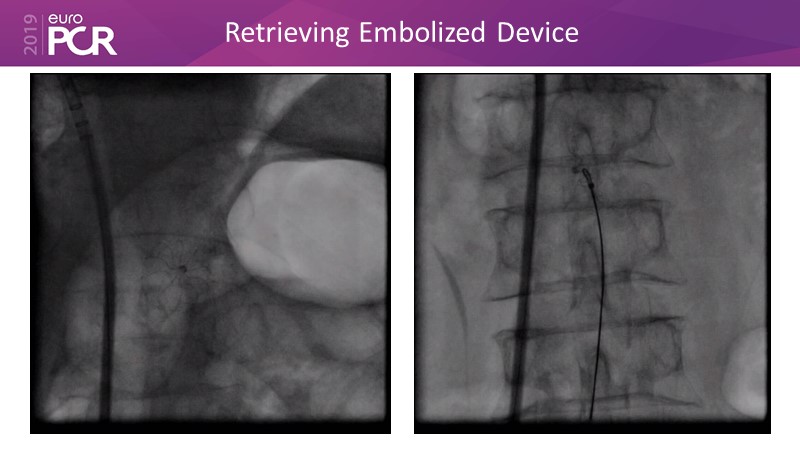

LAA closure

Left atrial appendage closure - A case-based discussion

Optimising procedural outcome and safety